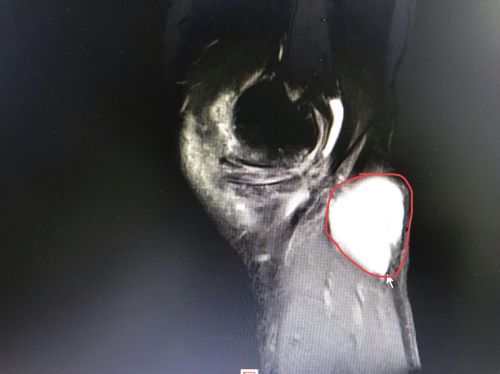

核磁共振可以清楚地看到囊肿的大小、形状。

王靖主任检查发现,罗先生左侧腘窝处有一约5cm大小包块,核磁共振结果显示:左侧腘窝囊肿、内侧半月板损伤。5月2 0日,王靖、贾真等专家为罗先生实施关节镜下腘窝囊肿清除、内侧半月板修整术。让罗先生喜出望外的是,术后几乎没有任何疼痛及不适感,术后第二天就可在扶双拐不负重的情况下下地。